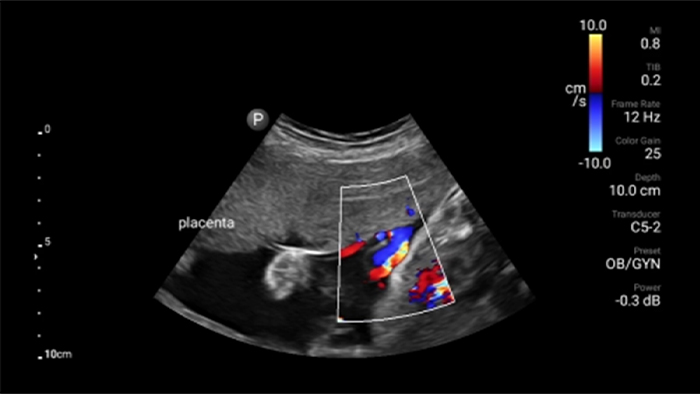

Lumify handheld ultrasound offers images that enhance diagnostic confidence.

See more when it counts

Lumify can help you make real-time decisions with more confidence, from assessment to recovery. Reveal the subtle details of an image, uncover enriched tissue definition with multiple angles and much more.